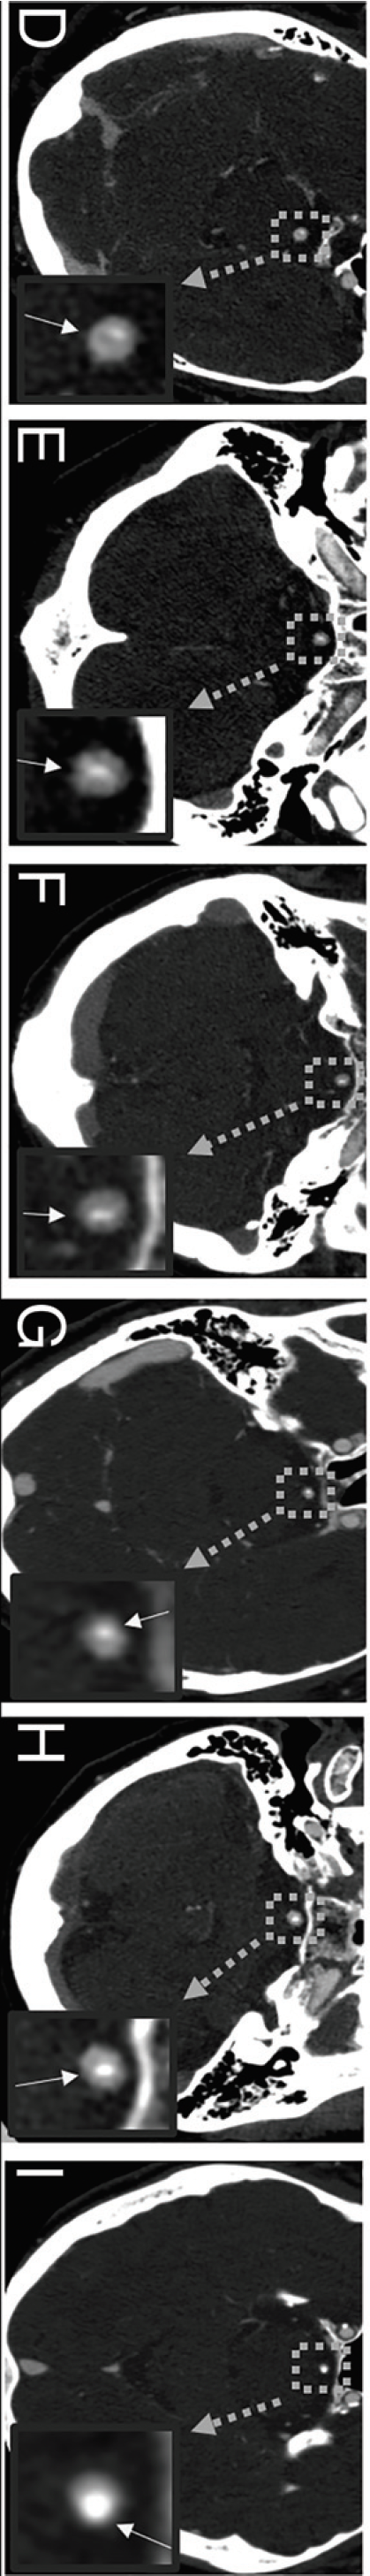

1. 几个基底动脉隔膜的病例可见结节样改变

第一例(A)的轴向CTA显示基底动脉隔膜的中心一个结节(放大插图,白色箭头)。另一个患者的轴向CTA图像(B)显示结节中央钙化(B放大插图,白色箭头)。第三例患者(C2)的轴向CTA可见部分钙化的结节样隔膜。在平扫CT轴位图像上,可见钙化(C1,箭头)。在轴位CTA(C2a放大插图,白色箭头)和冠状MIP(C2b,白色箭头)图像上可见部分钙化的结节:

2. 基底动脉隔膜钙化

13例(13/21,61.9%)可见基底动脉隔膜伴局灶性钙化。6例不同患者(D-I)的轴向CTA图像显示不同的钙化模式,其中一些显示为线样模式(D–F,箭头),其他显示为结节状钙化(G–I,箭头):